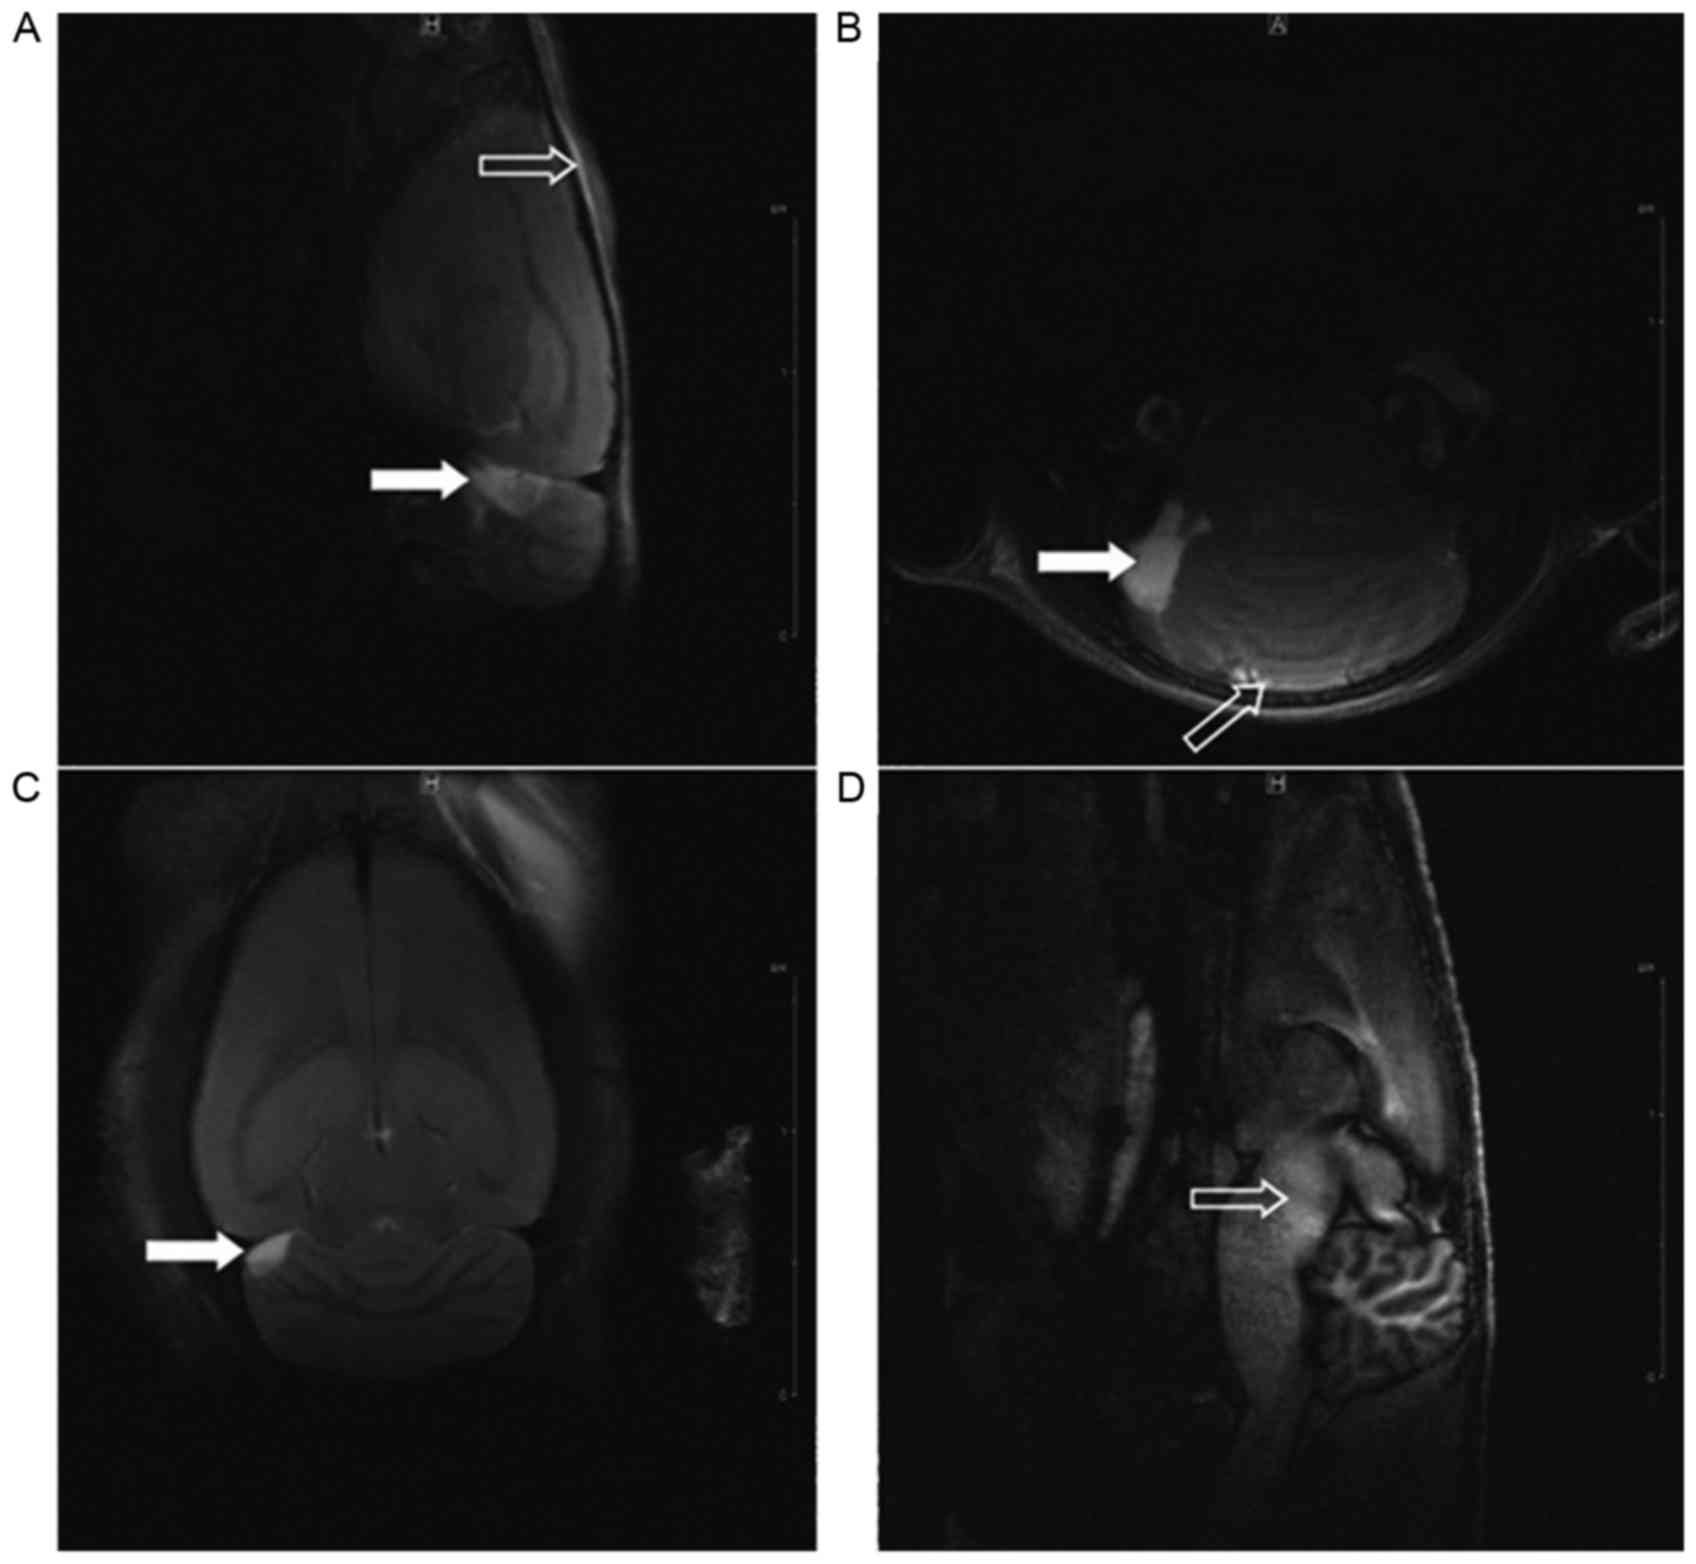

Although studies concerning blast‑related traumatic brain injury (bTBI) have demonstrated the significance of diffuse axonal injury (DAI), no standard models for this type of injury have been widely accepted. The present study investigated a mechanism of inducing DAI through real blast injury, which was achieved by performing instantaneous high‑speed swinging of the rat head, thus establishing a stable animal model of blast DAI. Adult Sprague‑Dawley rats weighing 150±10 g were randomly divided into experimental (n=16), control (n=10) and sham control (n=6) groups. The frontal, parietal and occipital cortex of the rats in the experimental group were exposed, whereas those of the control group were unexposed; the sham control group rats were anesthetized and attached to the craniocerebral blast device without experiencing a blast. The rats were subjected to craniocerebral blast injury through a blast equivalent to 400 mg of trinitrotoluene using an electric detonator. Biomechanical parameters, and physical and behavioural changes of the sagittal head swing were measured using a high‑speed camera. Magnetic resonance imaging (MRI) scans were conducted at 2, 12, 24 and 48 h after craniocerebral injury, only the experimental group indicated brain stem injury. The rats were sacrificed immediately following the MRI at 48 h for pathological examination of the brain stem using haematoxylin and eosin staining. The results indicated that 14 rats (87.5%) in the experimental group exhibited blast DAI, while no DAI was observed in the control and sham control groups, and the difference between the groups was significant (P<0.05). The present results indicated that this experimental design may serve to provide a stable model of blast DAI in rats.